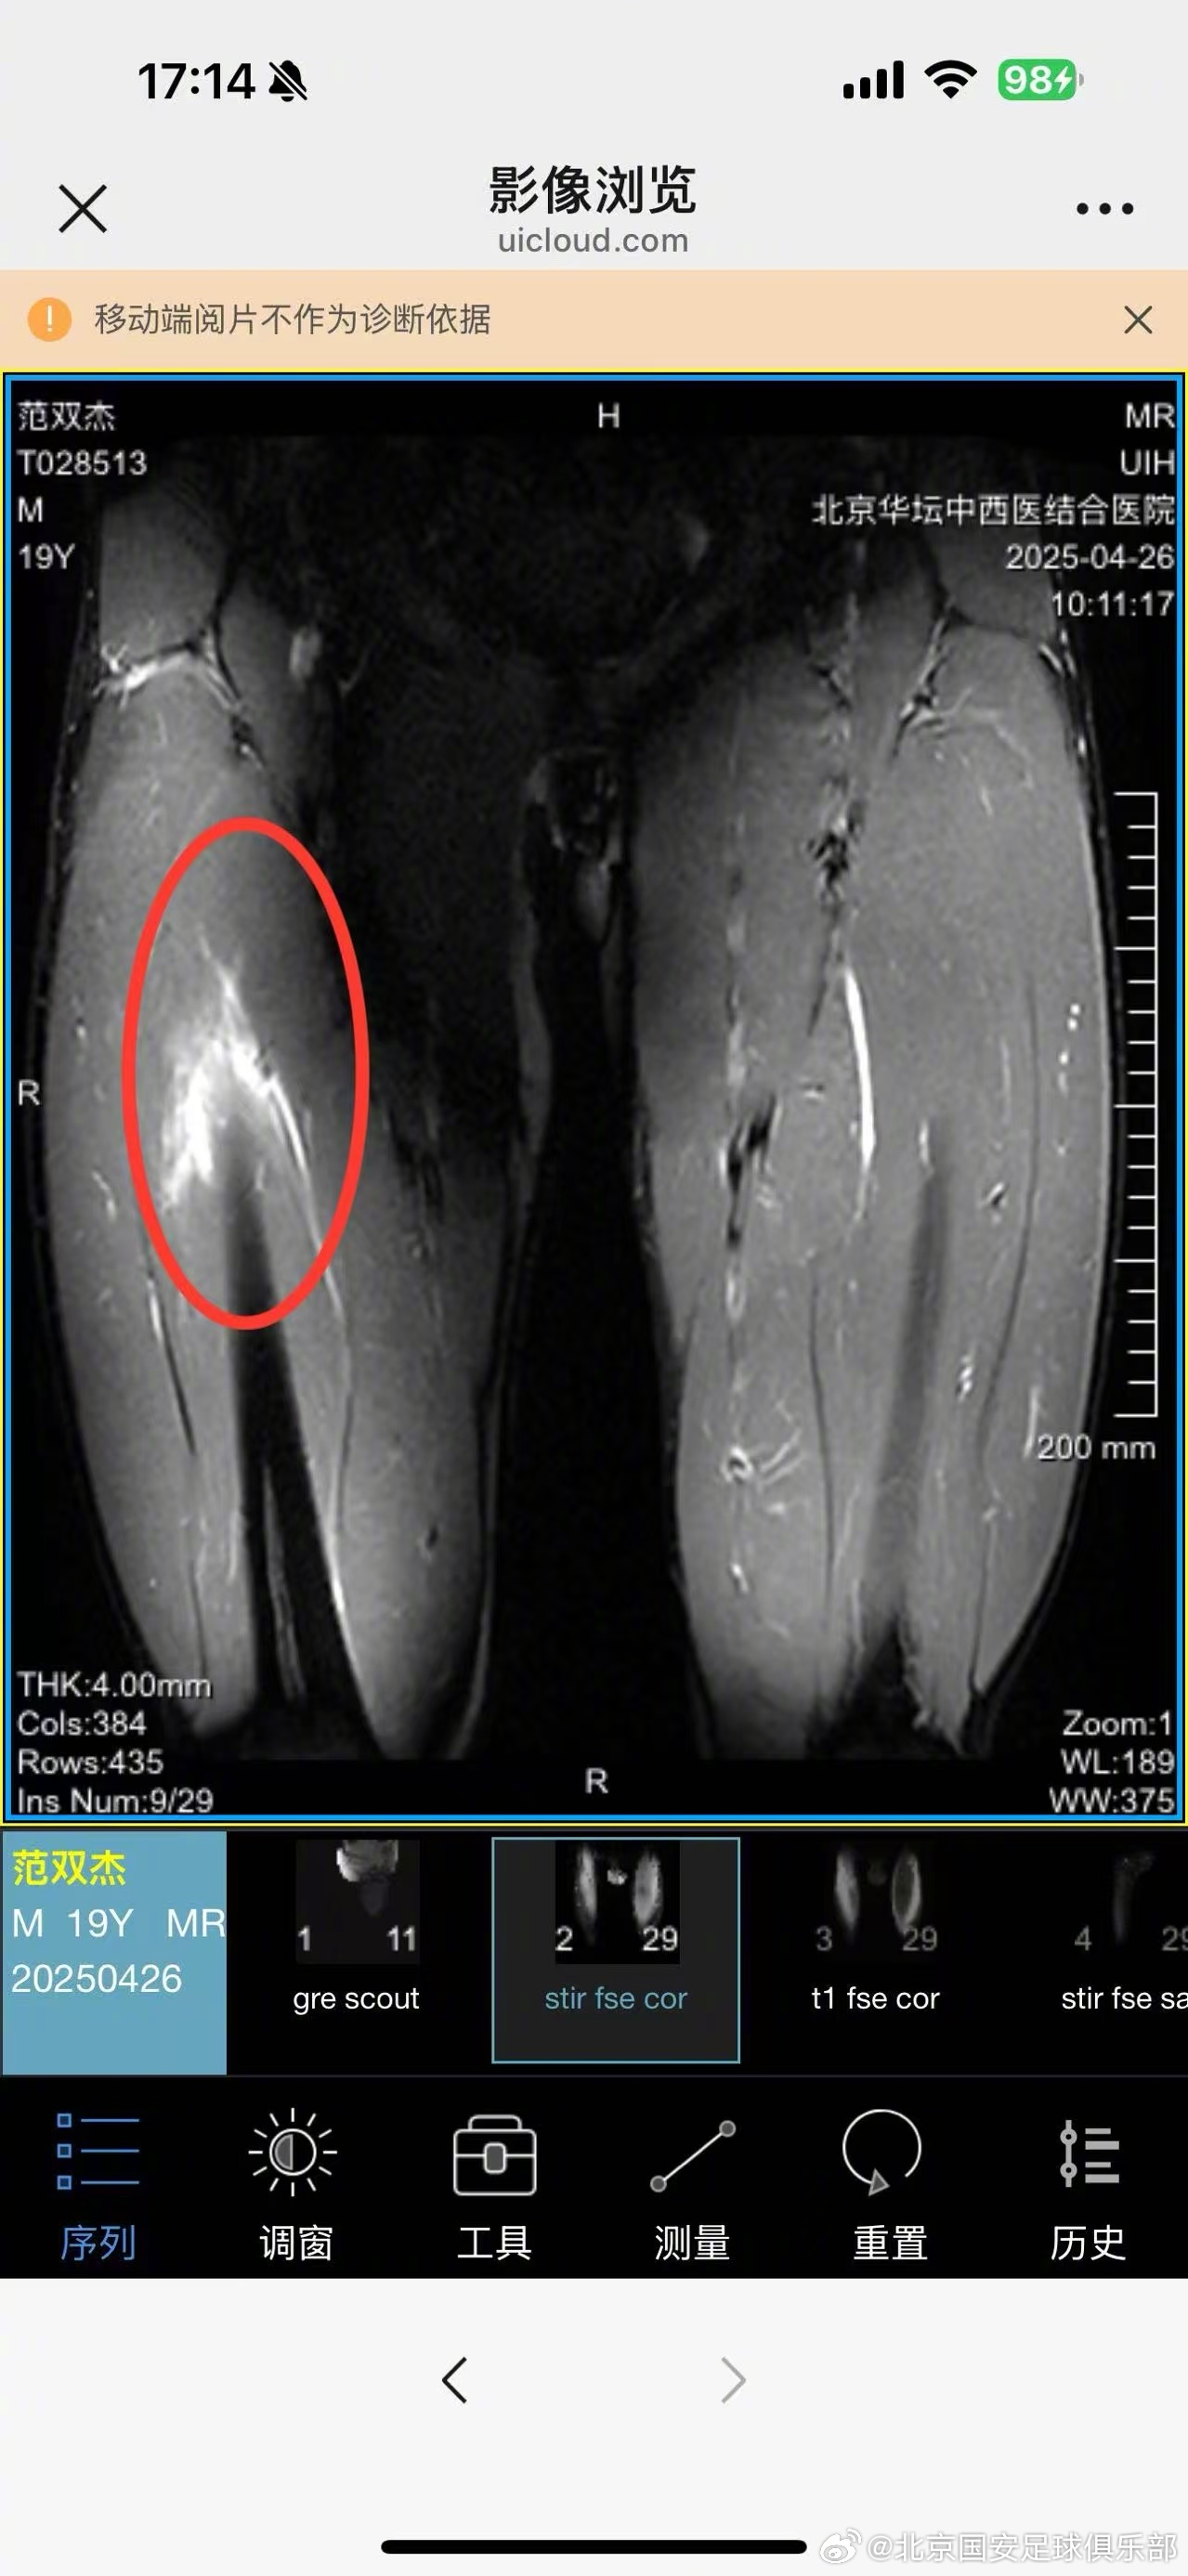

范双杰,4.25日主场对阵河南俱乐部酒祖杜康的比赛中,球员上半场比赛中左大腿受伤。伤后经核磁共振检查,显示左大腿缝匠肌肌腱拉伤,左大腿股直肌股外侧肌拉伤Ⅱ°。

目前症状:左大腿抬高疼痛4级(0-10)、行走痛4级、跑跳疼痛6-7级,髋膝关节灵活度优其他正常。

治疗方案:急性期对球员采取冷疗措施,24小时后进行激光、微波、热透、针灸等治疗;同时进行非疼痛下强化核心稳定性力量训练